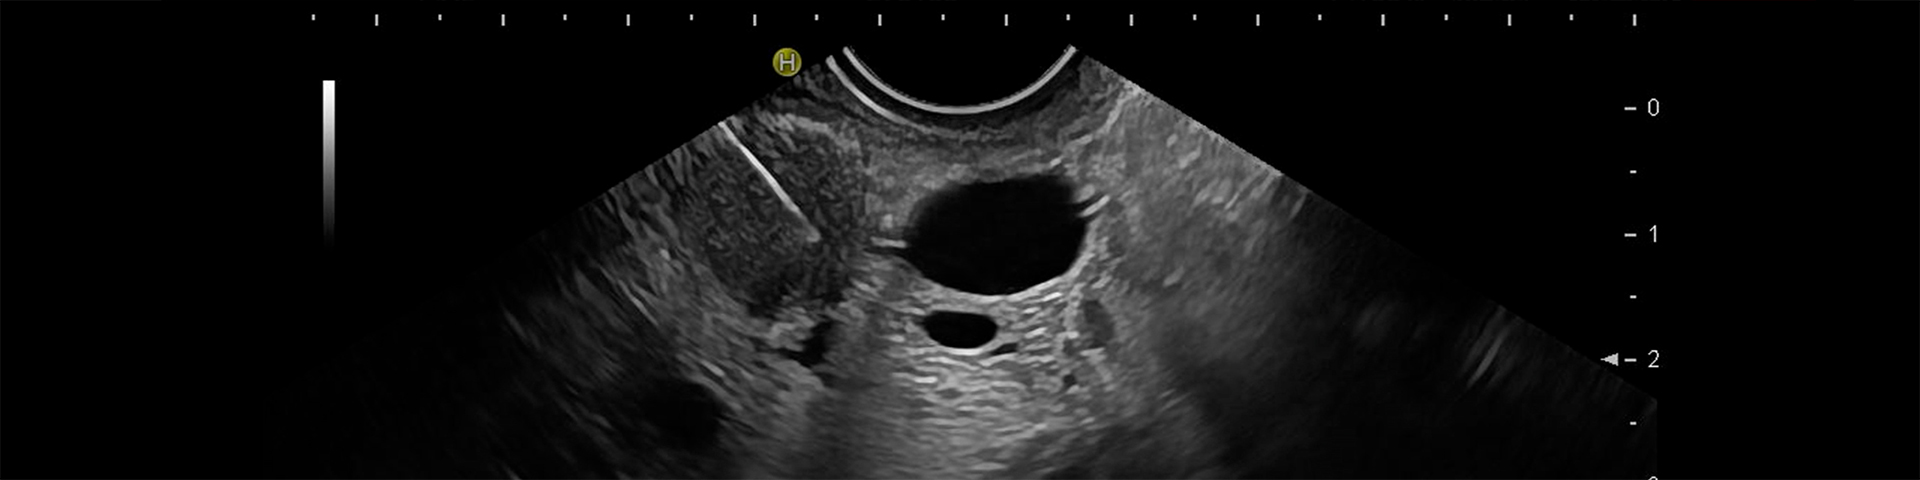

Endoscopic ultrasound (EUS) is a combination of endoscopy and sonography. With fine needle puncture, it is possible to obtain tissue from structures that are not accessible with other biopsy methods or only accessible with great invasiveness and the associated higher risk.

The primary field of application is the cytopathological diagnosis of tissue growth in the digestive system and the surrounding lymph nodes.